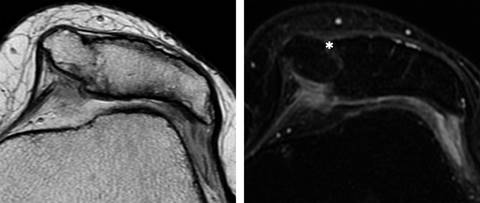

Los criterios diagnósticos de esta patología son:

Presencia de cartílago en la patela duplicada (Figura 4).

Figura 4: Resonancia magnética de rodilla izquierda donde se identifica patela accesoria medial a la patela en T2 axial en cortes finos y T2 con saturación grasa, donde se muestran ambas patelas con cartílago articular y con tejidos blandos de comportamiento hiperintenso que separa ambas patelas (*).

Presencia de una pseudoarticulación entre ambas patelas.

Aumento del área total de la patela.

Usualmente la patela accesoria tiene adherencias o estructuras, en apariencia, ligamentarias.